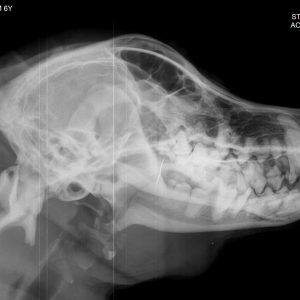

El diagnóstico por imagen es una herramienta fundamental en la medicina veterinaria moderna, ya que permite evaluar de forma precisa y no invasiva las estructuras internas del paciente. A través de técnicas avanzadas como la radiografía digital y la ecografía, es posible identificar alteraciones anatómicas y funcionales que facilitan un diagnóstico temprano y un manejo clínico más eficaz.

Nuestro servicio en Mastervet está orientado a ofrecer estudios de alta calidad, con equipos actualizados y protocolos adaptados a cada caso. Realizamos evaluaciones completas que incluyen la interpretación detallada de las imágenes y la emisión de informes clínicos claros, contribuyendo a la toma de decisiones terapéuticas.